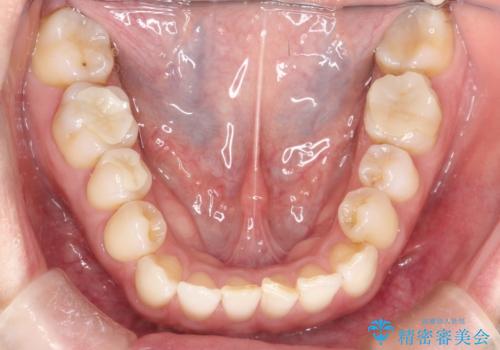

- 右上の前から2番目と3番目の歯が内側に引っ込んでしまっているのを主訴に来院されました。

右上の2番目と3番目のはが前後反対にかんでしまっている状態でした。